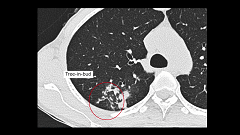

第10回 胸部CT 実践編 プレミアム対象

胸部CT読影において大切なのは、画像がどのような病態を反映しているか考えること。今回は実践編として、肺炎や肺結核、肺がん、胸水貯留など、さまざまな画像を提示します。まずは、大葉性肺炎と気管支肺炎のCT所見の特徴と代表的な起炎菌を整理。また、鑑別診断を行ううえで重要なヒントとなる結節の分布様式について解説します。肺がんや肺結核といった重要疾患の特徴的なCT所見をしっかり押さえましょう。